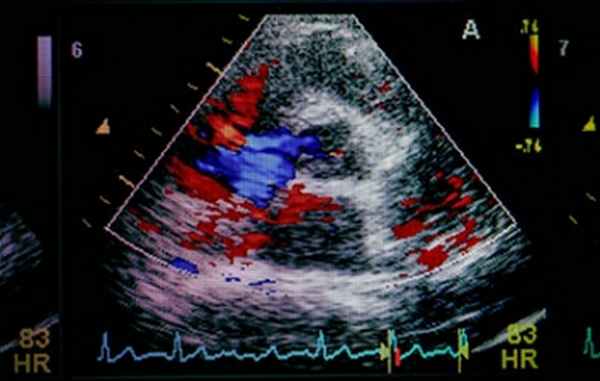

Цветовой допплер (Color Doppler). Цветовой допплер - аналог импульсного допплера, где направление и скорость кровотока картируется различным цветом. Так кровоток к датчику принято картировать красным цветом, от датчика - синим цветом. Турбулентный кровоток картируется сине-зелено-желтым цветом.

Цветовой M-модальный допплер (Color M-mode). Сопоставление M-модального режима и цветового допплера при проведении курсора через ту или иную плоскость, позволяет разобраться в фазами сердечного цикла и патологическим кровотоком.